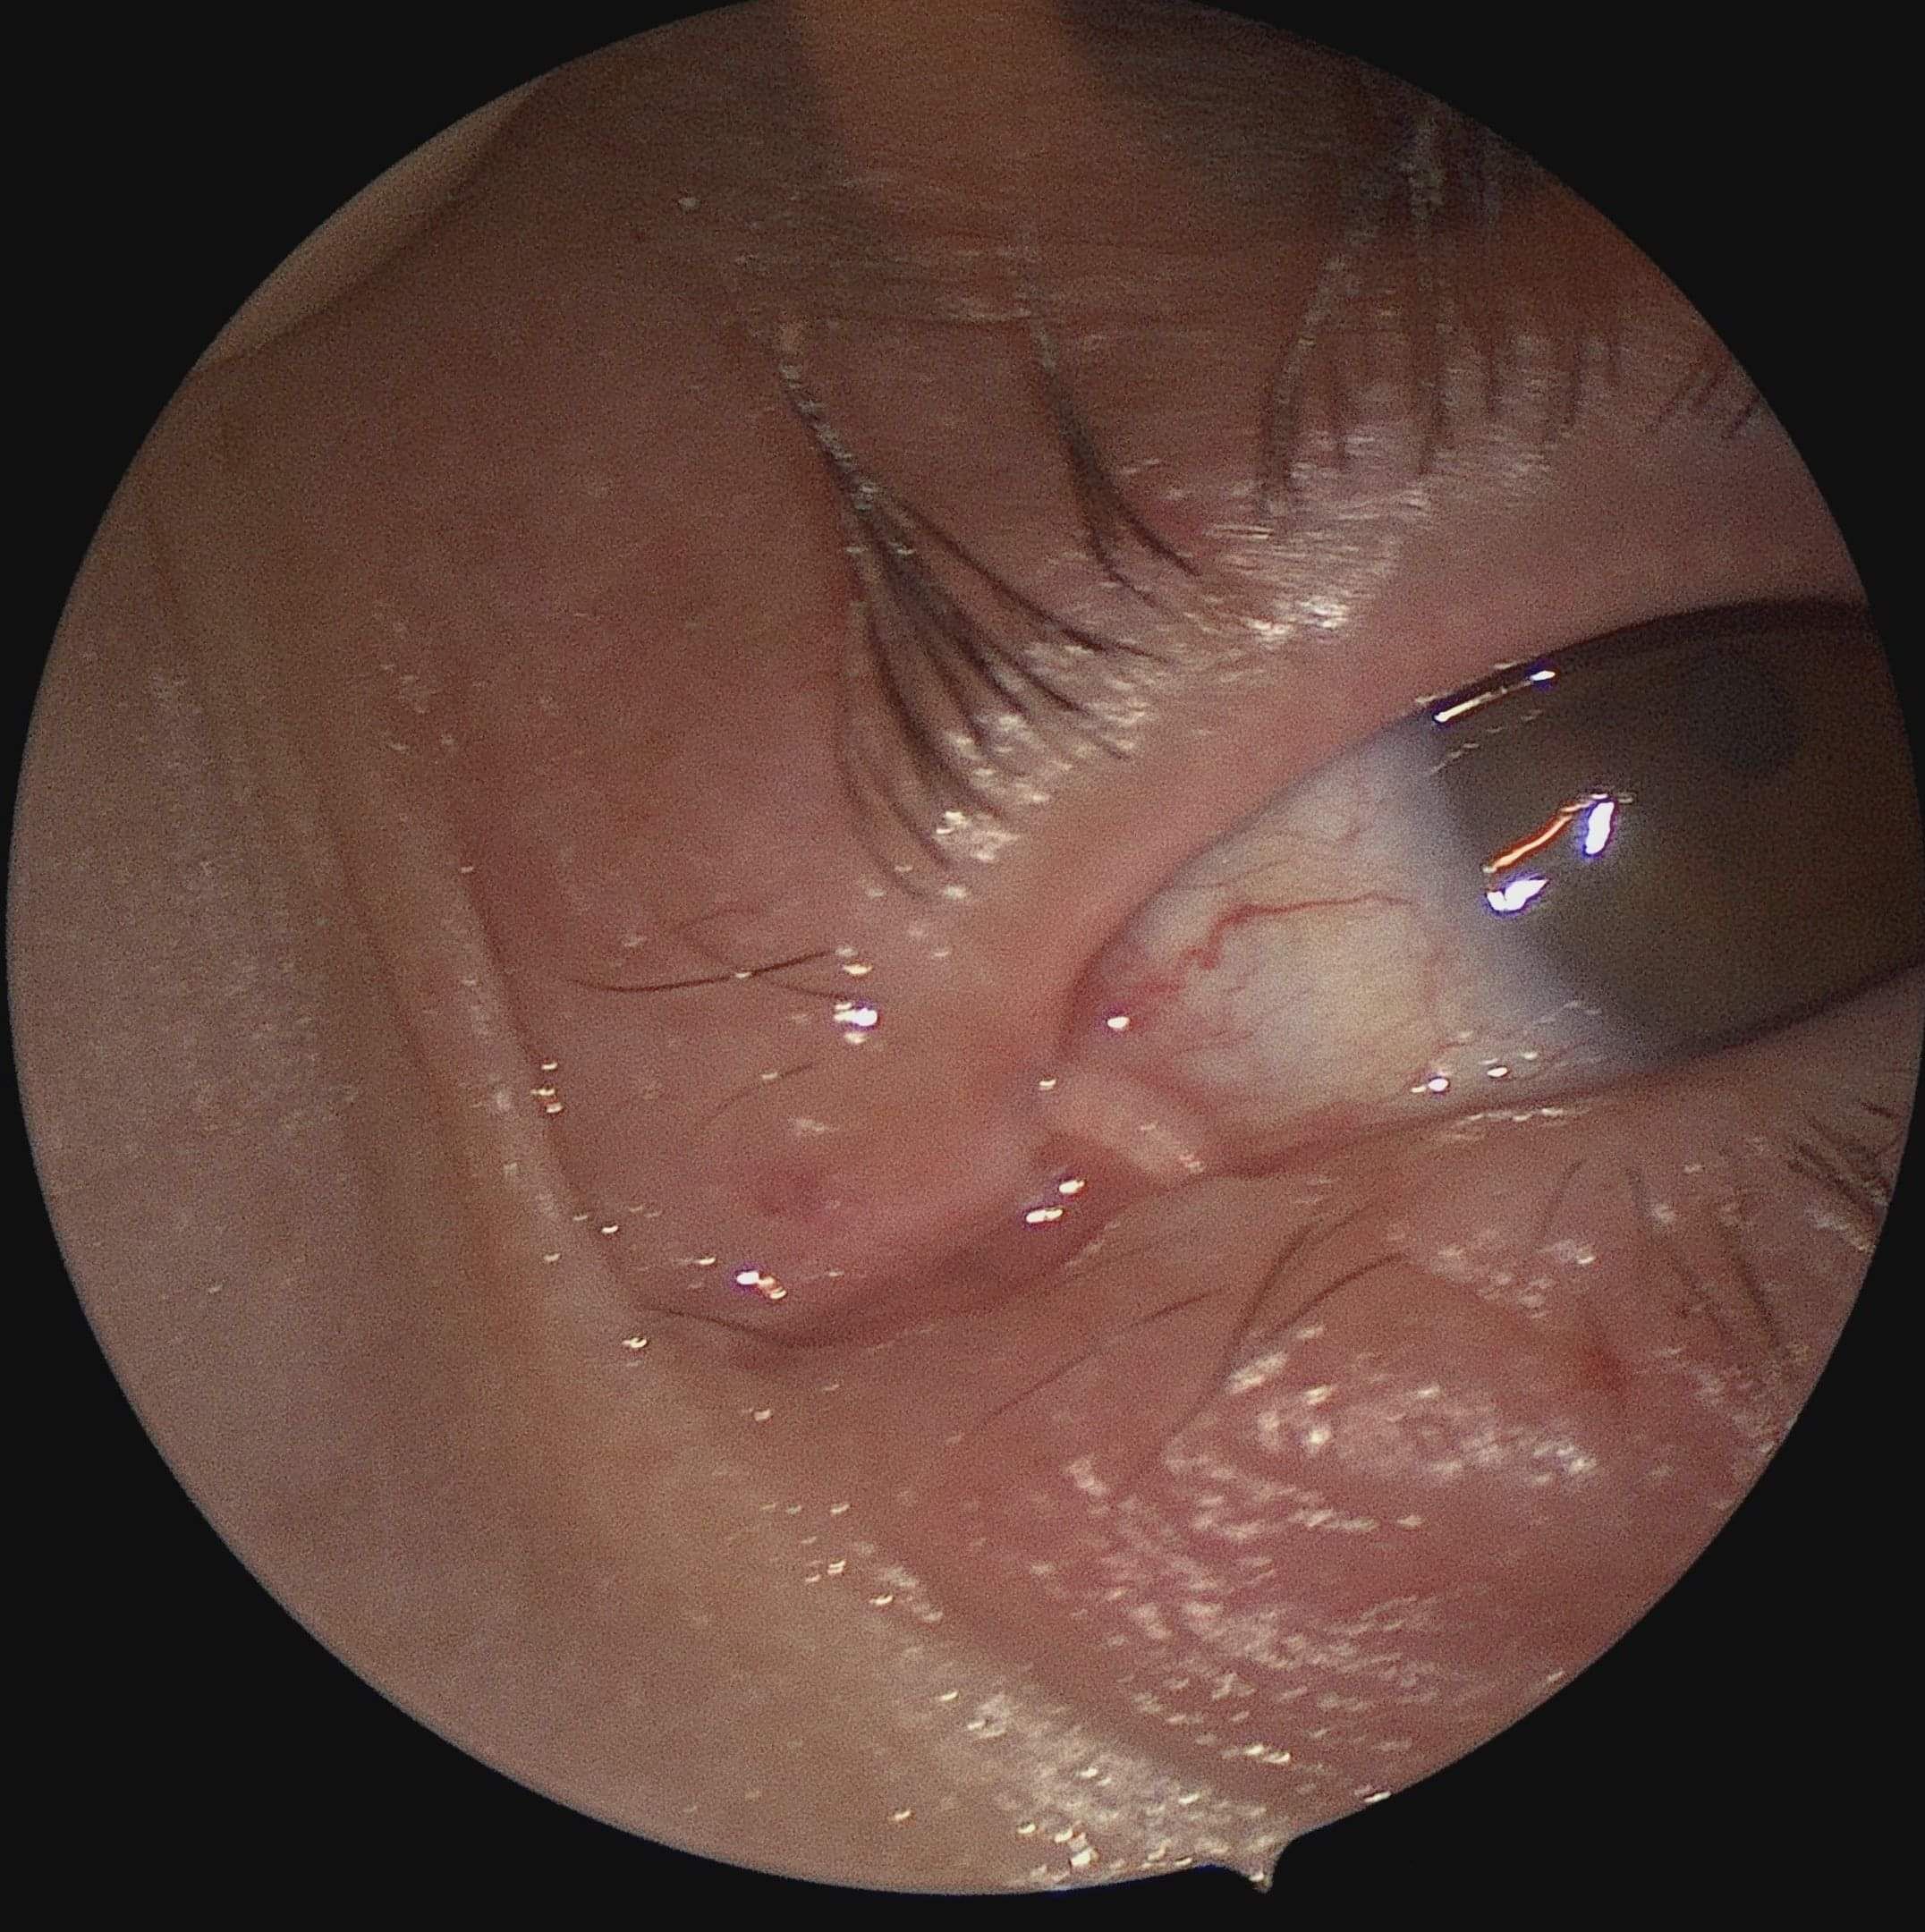

Endoscopic Oculoplastic Surgery refers to a transnasal surgical approach used to treat dacryocystitis (tear duct obstructions), orbital tumours and trauma to the eye in addition to aid in orbital decompression and optic nerve decompression. This procedure could also address various conditions affecting the eyelids, tear ducts, and surrounding structures within the eye socket.

Endonasal endoscopy is favoured for its minimally invasive approach to orbital lesions, particularly accessing the medial and inferior walls of the orbit effectively. ENT surgeons commonly perform endoscopic dacryocystorhinostomy (DCR) to address chronic dacryocystitis caused by nasolacrimal duct obstruction, typically seen in older adults. Optic nerve decompression involves relieving pressure on the optic nerve within its bony canal, often requiring urgent intervention within the first six hours after trauma for optimal visual recovery. Administering steroids decrease the oedema swelling and help to better vision loss.